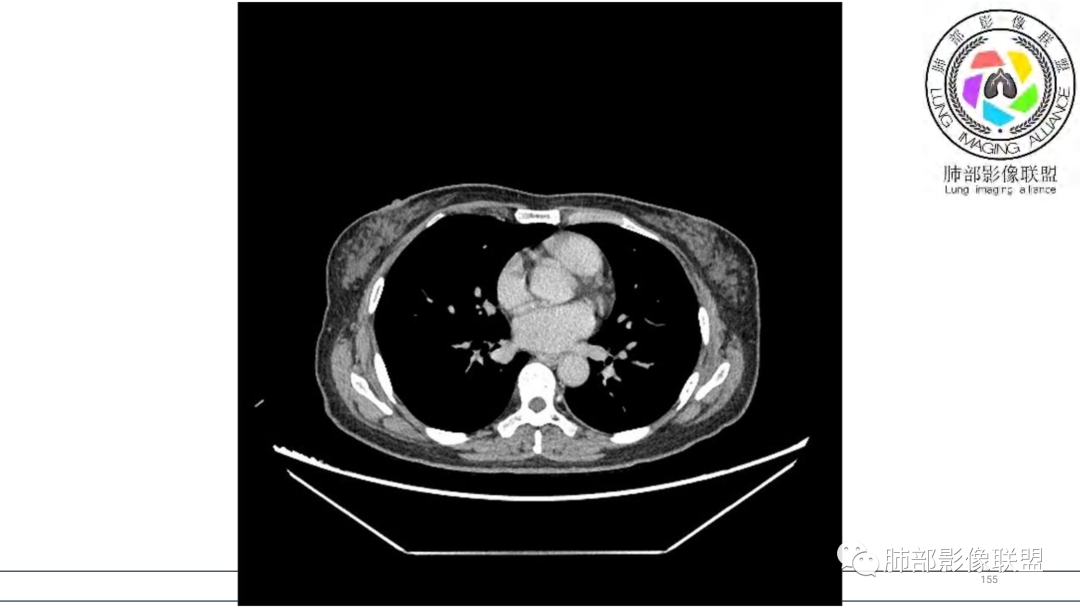

2.右肺下叶及中间段支气管后方类圆形块影,边界较清楚,未见分叶及毛刺,病灶部分突入支气管腔内(冰山一角),局部管腔狭窄,相应肺叶未见片影或体积变化。

3.块影密度均匀,未见液化坏死及钙化,渐进性强化,强化显著。

中青年女性,支气管管腔内外肿块(“冰山征”),边界较清楚,强化显著,未见阻塞性肺不张,尽管未出现“类癌综合征”临床表现,仍然符合典型类癌影像学表现。

类癌临床表现无特异性,影像学检查仍然是肺类癌的主要诊断依据。其特征性表现是孤立的、边界清楚的肿物,密度可均匀或不均匀,边缘多清楚锐利,部分病例可见浅分叶及毛刺。类癌侵及的支气管局部增厚,与正常的管壁分界清楚,局部呈乳头状突起,表面光滑。肺门旁肿块往往边缘光整、轮廓清楚、密度均匀,增强扫描大多呈均匀明显强化,可有持续强化或延迟强化。中央型肺类癌可引起支气管壁局限性增厚,形成轮廓光滑的管壁结节,并与腔外大病灶形成“冰山征”。少数病例可沿支气管腔内长轴生长,呈指套样改变,类似肺鳞癌,但较肺鳞癌血供丰富。